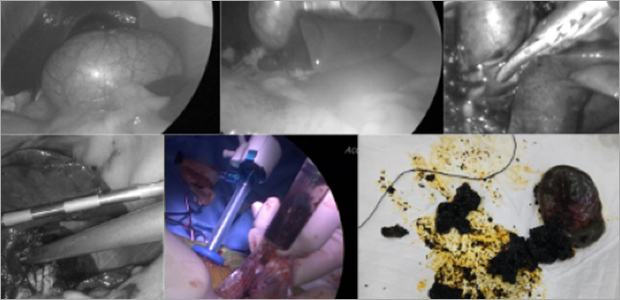

복강경 간생검

강아지 간생검 검사는 간질환의 원인을 알 수 있는 가장 정확한 검사입니다.

복강경 장비를 사용해 1cm이하의 절개창을 내어 간조직을 확보하고 조직검사를 진행할 수 있습니다.

출혈여부 직접 볼 수 있어 안전하고, 평가에 필요한 적절한 크기의 샘플을 얻을 수 있어 진단적 가치가 높은 방법이며,

수술적 개복을 통한 생검 방식에 비해 매우 작은 절개부 (1cm이하의 절개부 2부위)를 가지는 간생검 방식입니다.

케이스1

케이스2

- 수술 직후

- 수술 5일차

- 수술 3주차